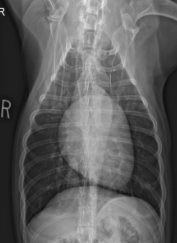

ID View

Right lateral